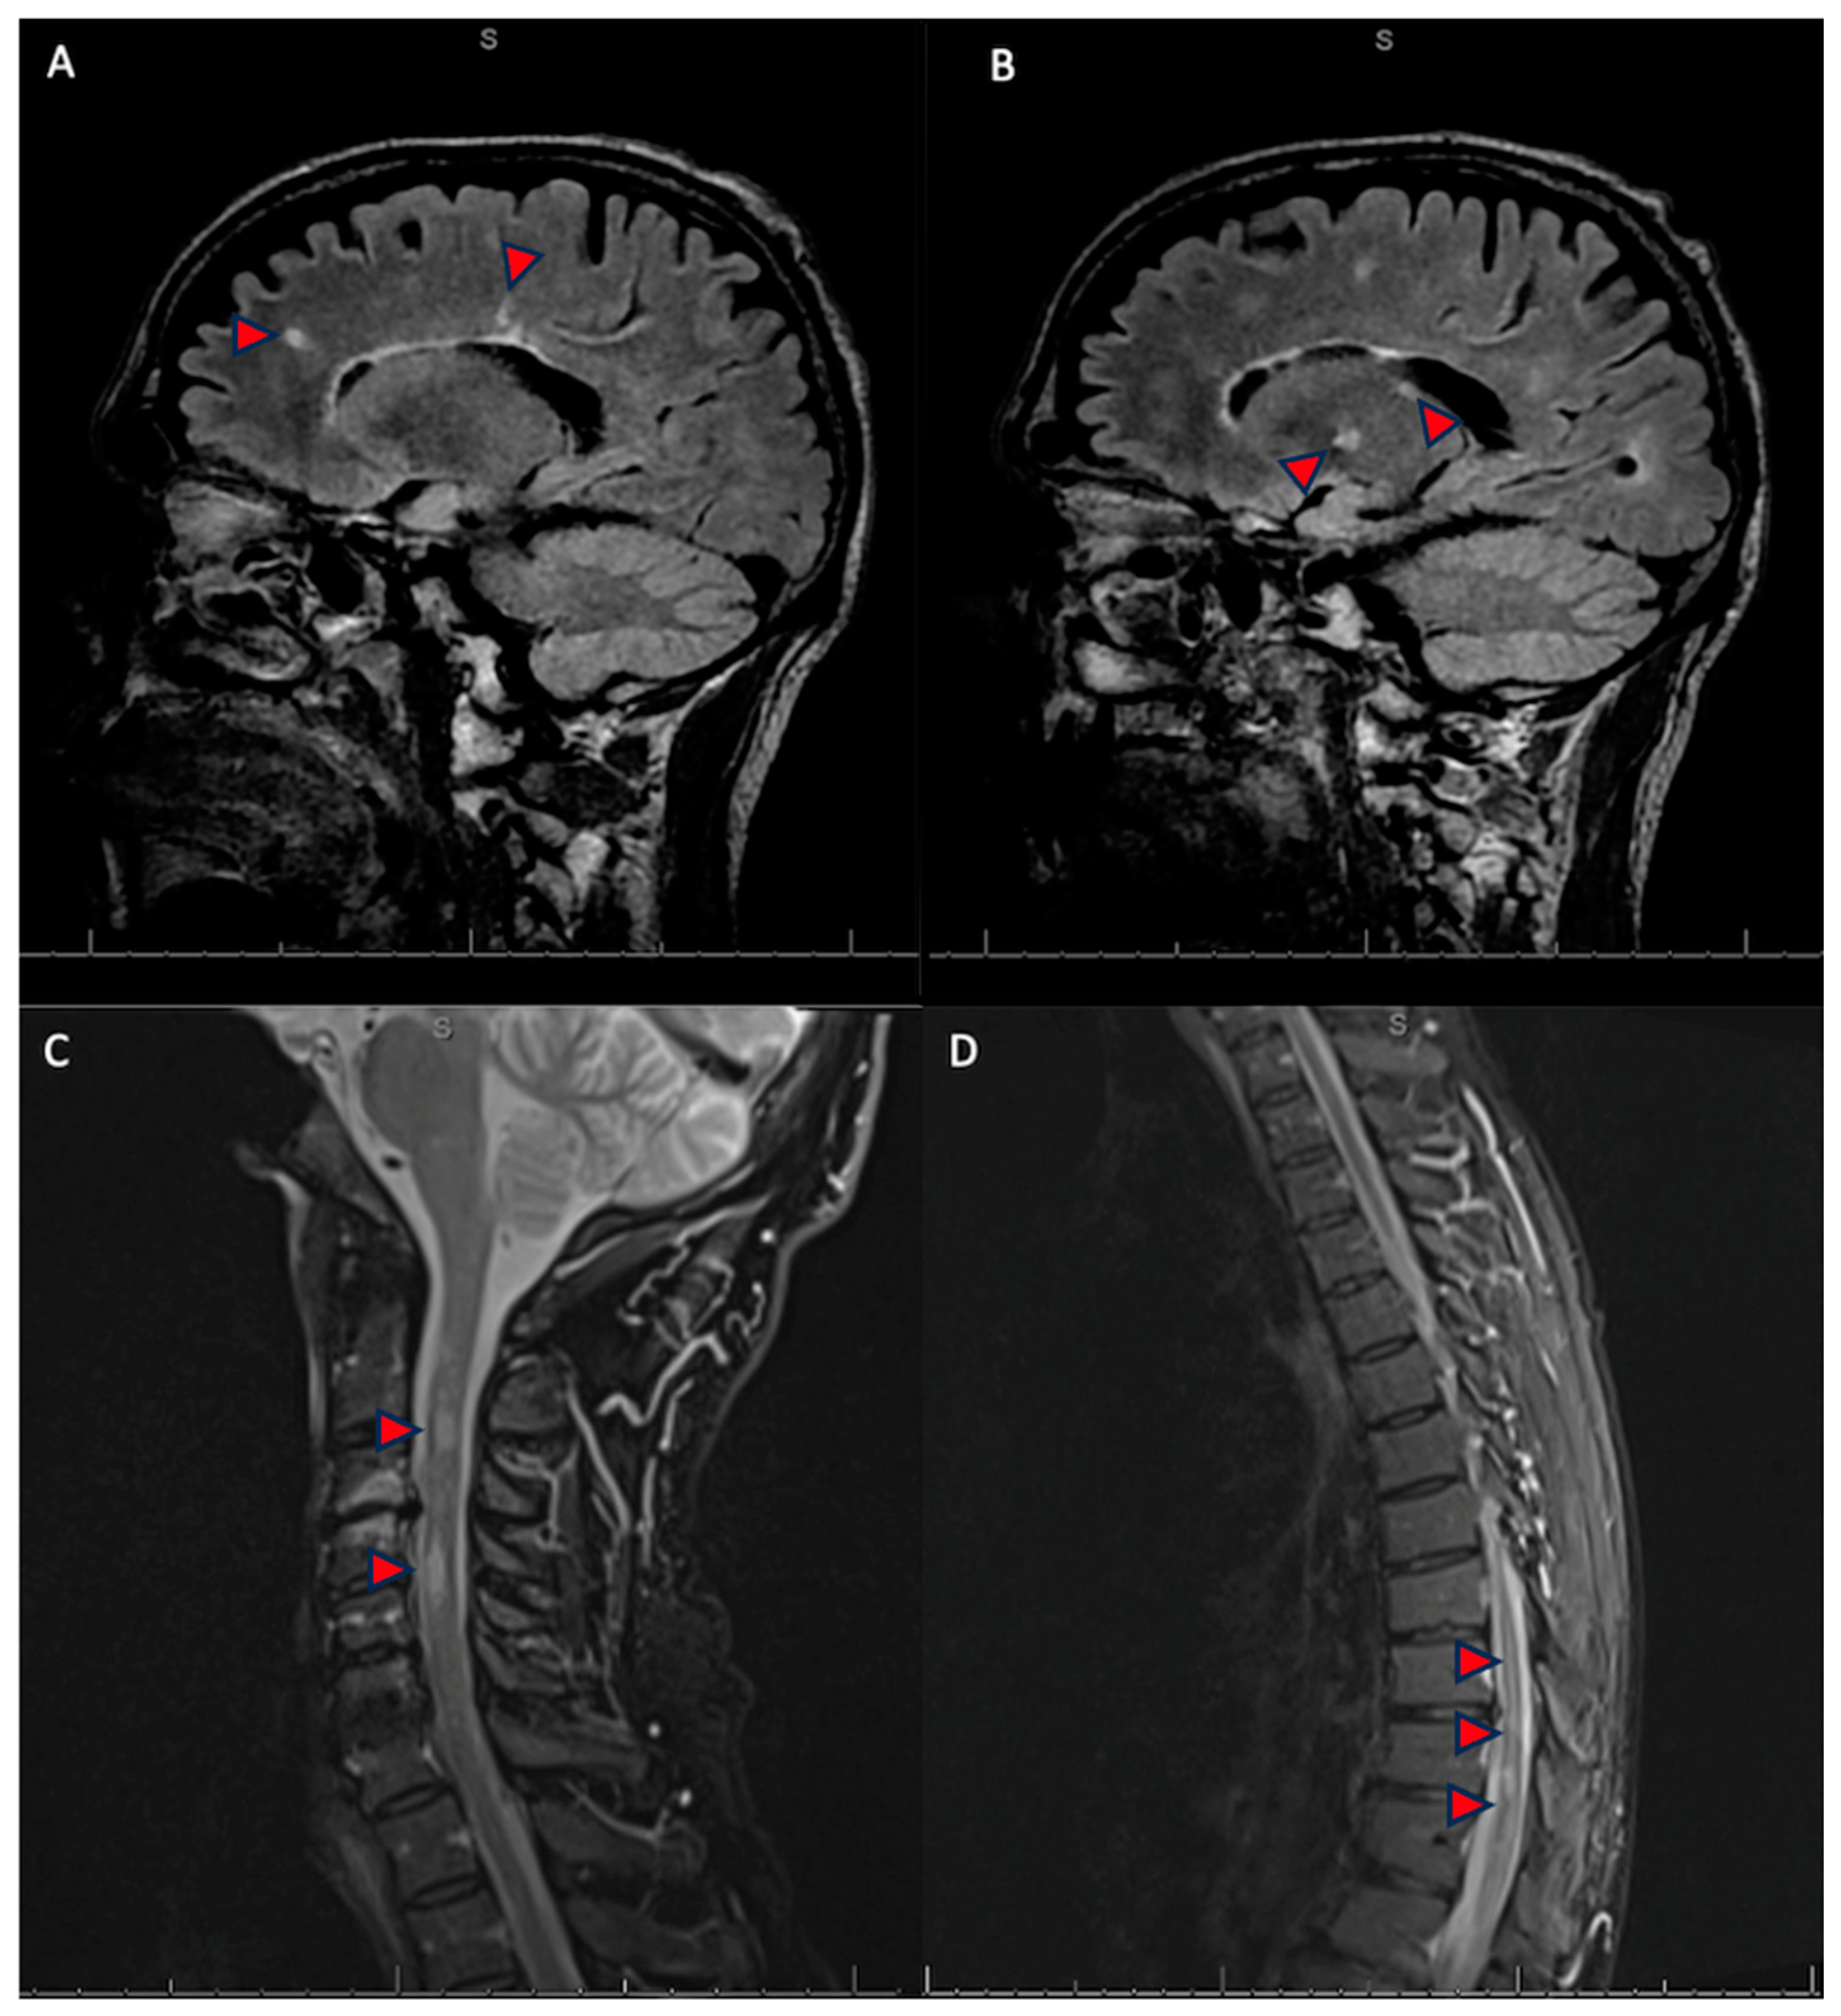

Co-Existent Central and Peripheral Demyelination: Related or Coincidental?

2. Case Presentation